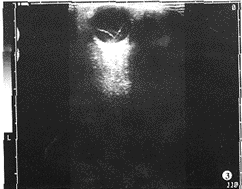

3.完全性视网膜脱离:脱离范围大,除视乳头和锯齿缘之外的全部视网膜层面分离,在玻 璃体无回声区内显示“V”字形带状回声,宽口向前方锯齿缘,窄口向后与视乳头连接(图 3),范围超过横向中心轴1/2。扫查平面与眼轴垂直时,玻璃体无回声区内可见小于球壁的 不规则环状回声,环内为玻璃体液,环外为视网膜下液。新鲜视网膜脱离表现无伴随改变 ,脱离均匀,活动好。陈旧性视网膜脱离有伴随改变,视网膜迂曲、增厚、不均,因发病时 间长而发生机化或囊性变,带状回声的形态、厚薄不一致,甚至皱缩、不活动(图4)。

图3 完全性视网膜脱离,玻璃体无回声区出现“V”字形带状高回声